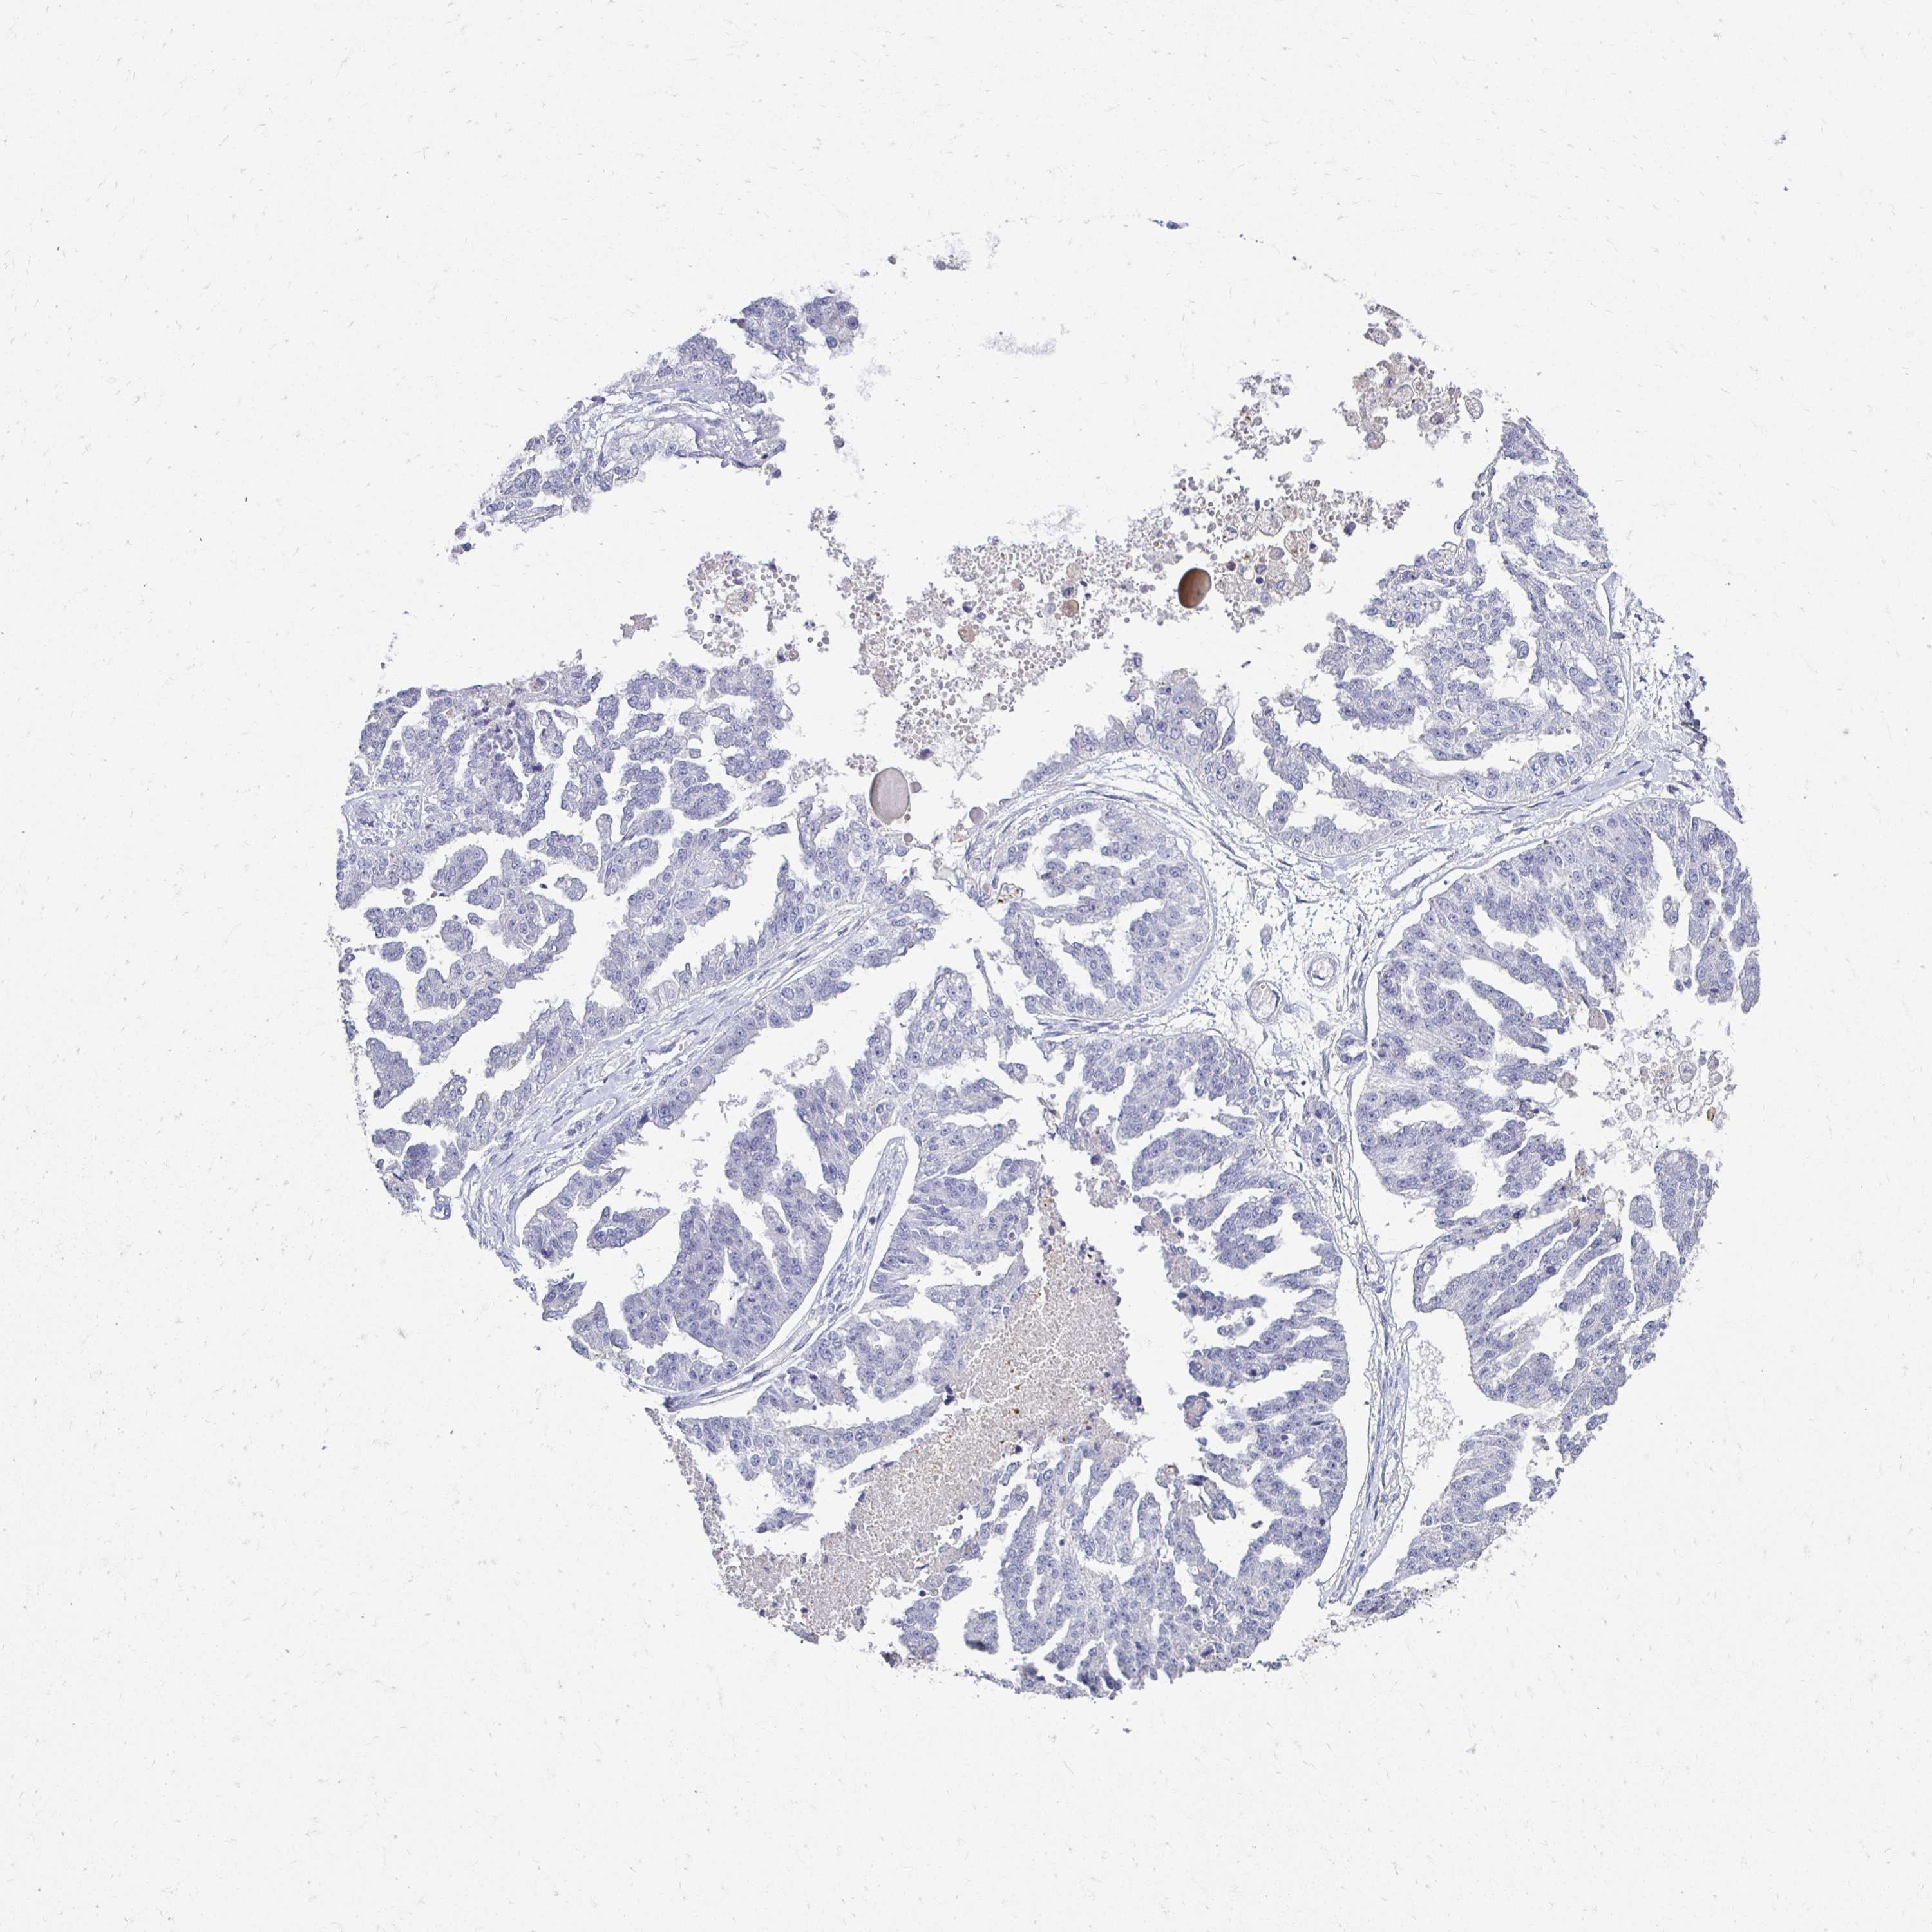

OVARIAN CANCER - Protein expressioni

A mouse-over function shows sample information and annotation data. Click on an image to view it in a full screen mode. Samples can be filtered based on level of antibody staining by selecting one or several of the following categories: high, medium, low and not detected. The assay and annotation is described here.

Note that samples used for immunohistochemistry by the Human Protein Atlas do not correspond to samples in the TCGA dataset.

Antibody stainingi

Antibody staining in the annotated cell types in the current human tissue is reported as not detected, low, medium, or high, based on conventional immunohistochemistry profiling in selected tissues. This score is based on the combination of the staining intensity and fraction of stained cells.

Each image is clickable and will lead to virtual microscopy that enables deeper exploration of all samples and also displays staining intensity scores, fraction scores and subcellular localization as well as patient and tissue information for each sample.

Antibody HPA048741

Antibody CAB001983

Staining

High

Medium

Low

Not detected

Intensity

Strong

Moderate

Weak

Negative

Quantity

>75%

75%-25%

<25%

None

Location

Nuclear

Cytoplasmic/membranous

Cytoplasmic/membranous,nuclear

Cystadenocarcinoma, serous, NOS

Carcinoma, NOS

Cystadenocarcinoma, mucinous, NOS

Carcinoma, endometroid